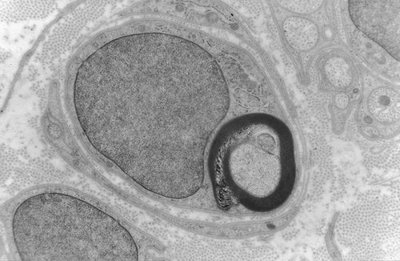

Dans le SNP tu as les myélinisée et les amyélinisée , bon avec la myéline tu as l'air de savoir donc pour les amyélinisée tu as bien une gaine ce sont celles ayant deux types : dans les deux les axones sont recouverts du cytoplasme de la cellule de Schwann dans le type un les axones sont indépendant et dans le type 2 regroupé en faisceau , tout cela relié a l'extérieur par le mésaxone.

Donc un axone est bien recouvert d'une gaine ( en sachant que la gaine de myéline c'est le mésaxone qui s'est enroulé autour de l'axone or dans les amyélique le mésaxone ne s'est pas enroulé ) sauf qu'on ne l'appelle pas gaine de myéline .

Ci joint une photo qui est dans ta ronéo et qui appuie mes dires .

Image

Uploaded with ImageShack.us